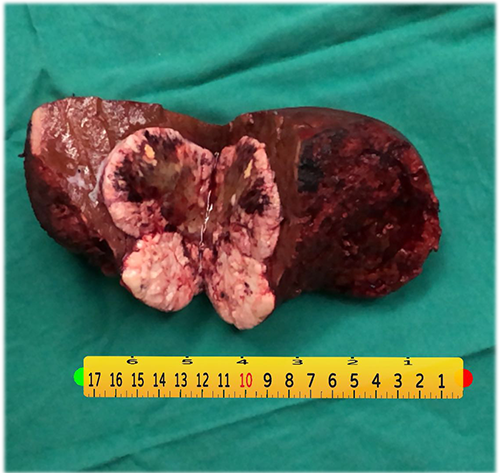

右肝癌----S567切除